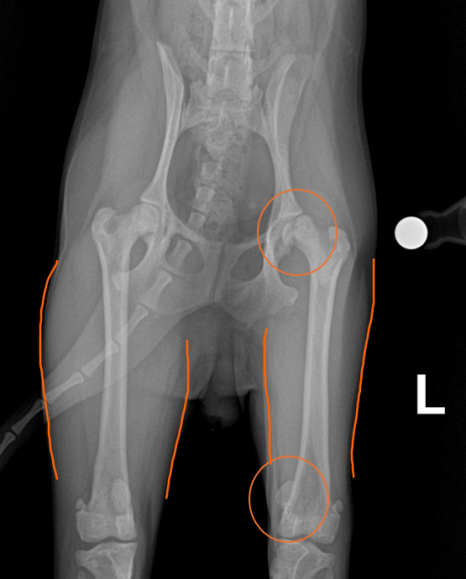

위 강아지 환자는 X-RAY 사진 상, 왼쪽 고관절의 골두가 녹아내려 쪼개진 모습이 확인되었습니다. 명확하지 않은 이유로 골두의 영양분을 공급하는 혈관이 괴사되는 골두무혈성괴사증(LCPD)의 전형적인 모습입니다. 또한 슬개골 탈구가 같이 확인되었으며, 위 고관절 문제로 인하여 왼쪽 뒷다리에 체중지지를 하지 못해 오른쪽에 비해 대퇴사두근의 위축이 확인되었습니다.

강아지 소형견 인공관절 및 슬개골탈구 수술 후 엑스레이 사진 출처: 에스동물메디컬센터